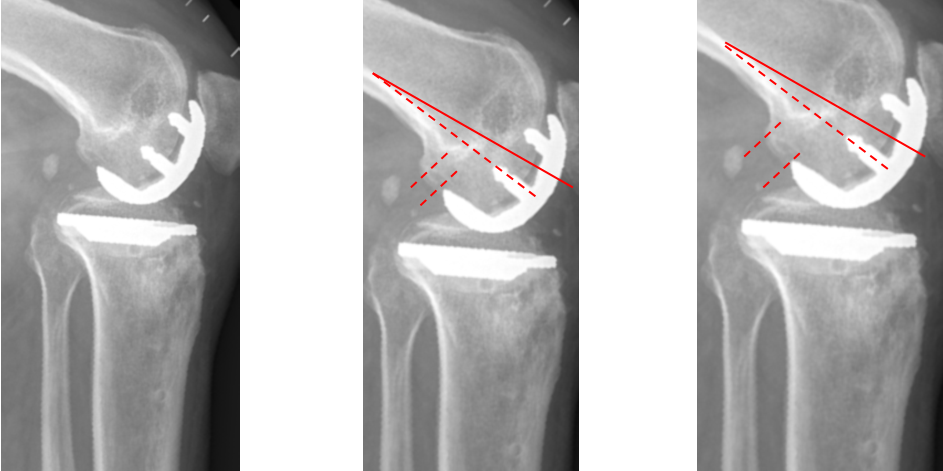

股骨后髁过截

外侧股骨髁坏死伴发育不良。

股骨假体过屈

外侧单髁术后股骨后髁过截,股骨假体过屈(45°)。